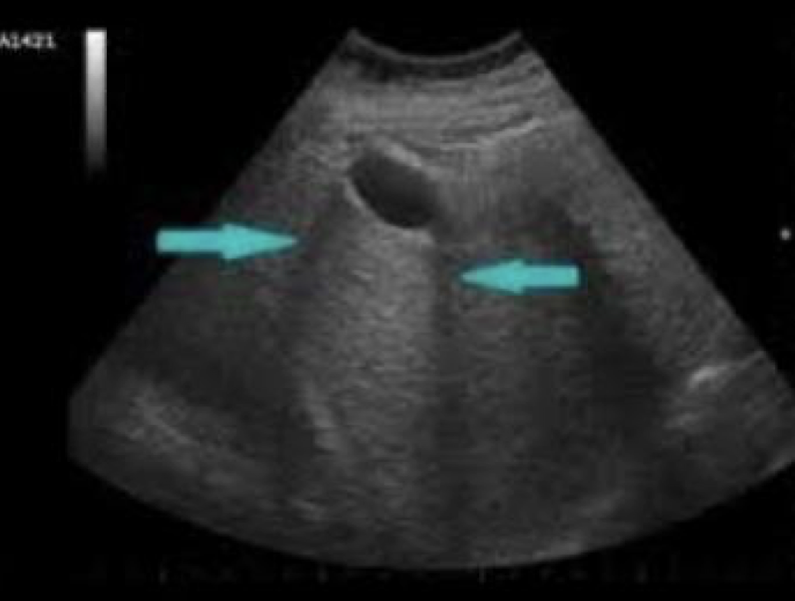

when sound waves bend as they hit a curved surface tangentially

edge-shadowing artifact

What artifact is this showing?